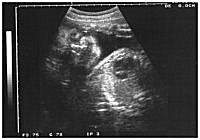

despues de tanto desmadre de vida ocurrió esto............